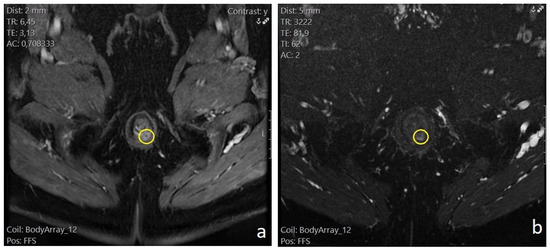

Trainees and attending radiologists were involved in the MR imaging. The MR images were finally evaluated by one radiologist with 20 years of experience who was blinded to whether the patient would also be subjected to a 3D-EAUS or not. The anal sphincter muscles, levator plate, and ischiorectal fossa were evaluated with a T1 sequence before and after gadolinium infusion. The lumen of the perianal fistulas and any secondary extensions or inflammatory liquid collections were visualized as hyper-intense tracts or cavities on T2- and STIR-weighted images. On gadolinium-enhanced fat-suppressed T1-weighted images, the fistulous tract’s wall and active granulation tissue demonstrated intense enhancement, while any fluid in the lumen was hypointense. Fibrotic scar tissue demonstrated low signal intensity on both T1- and T2-weighted images. We recorded the four characteristics mentioned in the 2.6. Methods subchapter for all visualized perianal fistulas (Figure 1 and Figure 2).

Figure 1. Patient no. 1; preoperative pelvic MRI. (a) T1 fat-saturated sequence with intravenous contrast, axial plane. Intersphincteric perianal fistula, located at the posterior wall (5 o’clock) of the anal canal (yellow circle). Intense enhancement of the fistulous tract wall. (b) T2 fat-sat, axial plane. The same 5 o’clock intersphincteric perianal fistula (yellow circle). Hyperechoic visualization of the fistula lumen.